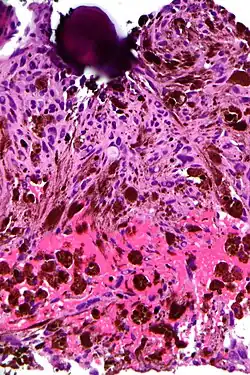

Psammoma bodies usually have a laminar appearance, are circular, acellular and basophilic.